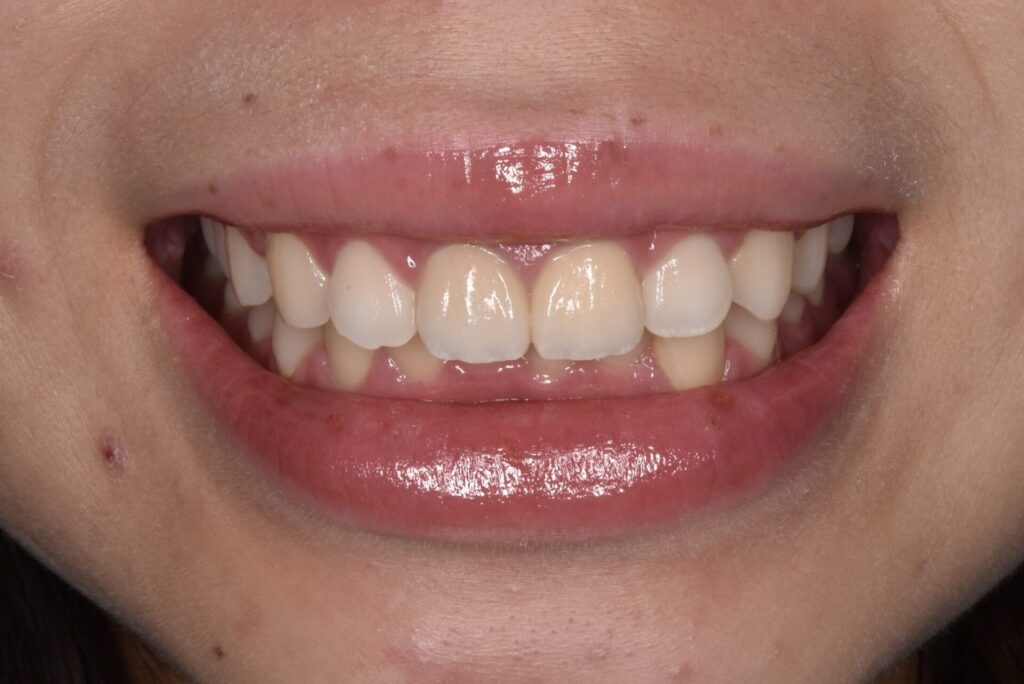

右の前歯の歯ぐきの黒ずみと古い被せ物のやりかえ治療をしています。歯の高さが左右で違うため歯肉整形をしています。*さくらセラミックプラン